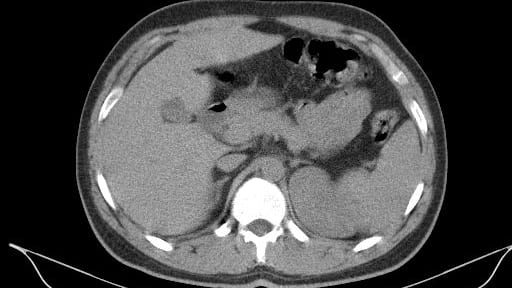

Aspiring bikini model Bea Amma, 23, contracted a drug-resistant flesh-eating infection after receiving fat-dissolving shots at an unlicensed med spa in California. The infection, caused by contaminated vials, left her with severe skin damage and mounting medical bills. Despite attempts to sue the spa, Bea faced legal setbacks due to the spa's lack of insurance. She now shares her story on social media to raise awareness about the risks of unregulated cosmetic procedures.